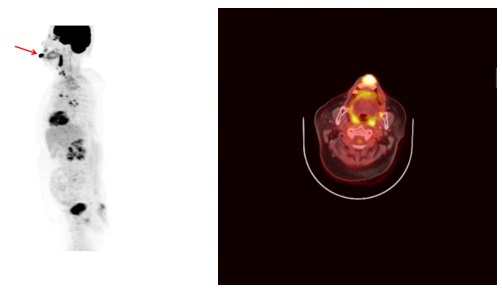

② 양전자방출단층촬영(Positron Emission Tomography, PET)

양전자방출단층촬영(PET)은 각 장기의 생화학적, 생리적 반응을 정량화하여 진단, 치료방침설정 등에 활용하는 영상기법으로 양전자의 방출 후 나타나는 광자를 검출기를 통해 검출하는 것을 기본원리로 합니다.

구강점막 등에 발생한 악성 흑색종에 대한 병기 결정에도 도움이 되는 것으로 알려져 있습니다.

[아랫입술에 발생한 구순암의 양전자방출단층촬영(PET) 영상]